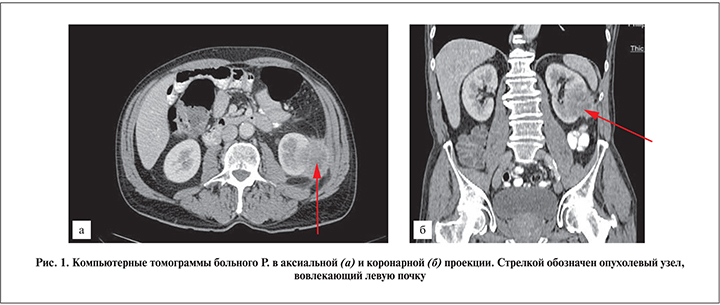

При КТ органов грудной клетки, брюшной полости и органов малого таза от 02.02.2018 в прямой кишке был выявлен опухолевый узел до 2,7 см в диаметре с преимущественно внекишечным расположением и вовлечением семенных пузырьков и поражением регионарных лимфатических узлов. Также в области нижнего полюса левой почки с его вовлечением расположено опухолевидное образование размером 6,3×4,7×5,1 см, распространяющееся на брюшину левого латерального канала, врастающее в левую косую мышцу живота (рис. 1). Однозначно высказаться о характере данного образования на дооперационном этапе было затруднительно. На основании проведенного обследования и приняв во внимание данные анамнеза заболевания, КТ, колоноскопии, гистологического исследования биопсийного материала, больному был установлен диагноз «метахронный карциноматоз с вовлечением почки и прямой кишки».